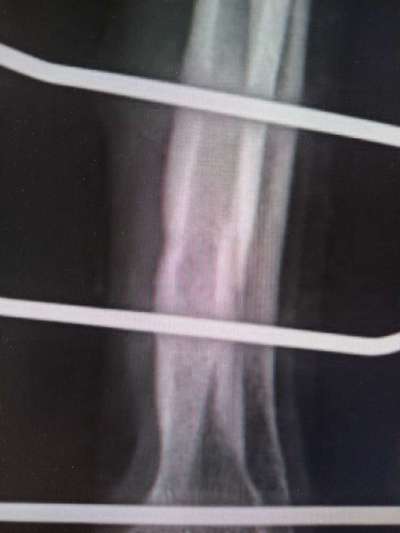

Aufgrund dieser Röntgenaufnahmen wurde am 25.10.23 beschlossen, dass der Fixateur entfernt werden kann.

Auf diesen Aufnahmen, die direkt nach der Entfernung des Fixateurs gemacht wurden, kann man gut erkennen, warum Lucy wieder / noch geschont werden muss.

Mal wieder sind es ihre dünnen Knochen in Verbindung mit ihrem Temperament, die die extreme Schonung erforderlich machen. Sonst bricht der Knochen aufgrund der Löcher, die durch die Fixateur-Drähte entstanden sind.